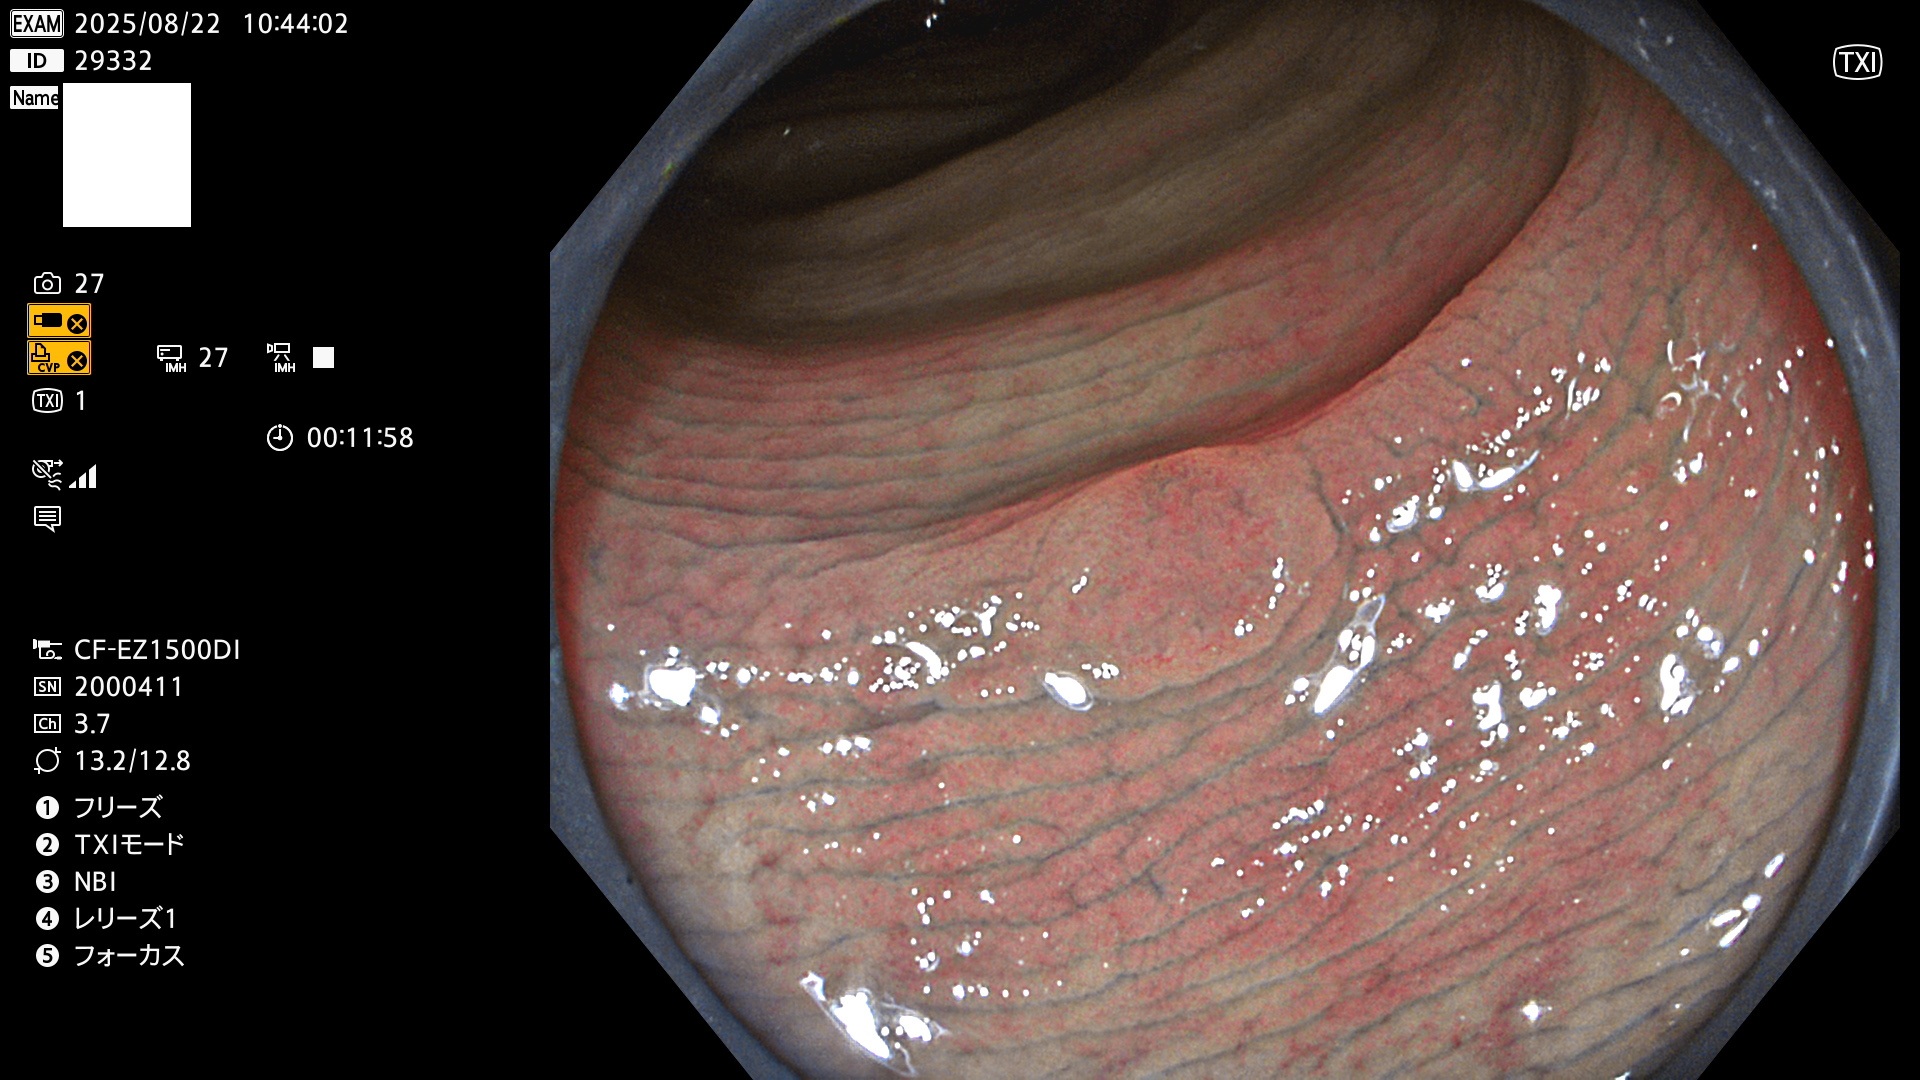

完全に平坦な物をUb、陥凹している物をUcと呼びます。Ubは認識が困難で、Ucはびらん(炎症)と紛らわしいために見落とされやすく、「内視鏡後・大腸癌」の原因になります。

毎週の検査(木・金・土・日)に発見されたUbとUc型・腺腫を、その週の日曜の夜にUPし1週間、提示します。

2025年8月21日〜8月24日の4日間(30件)5個 (Uc_ADR=3個/35人=14%)